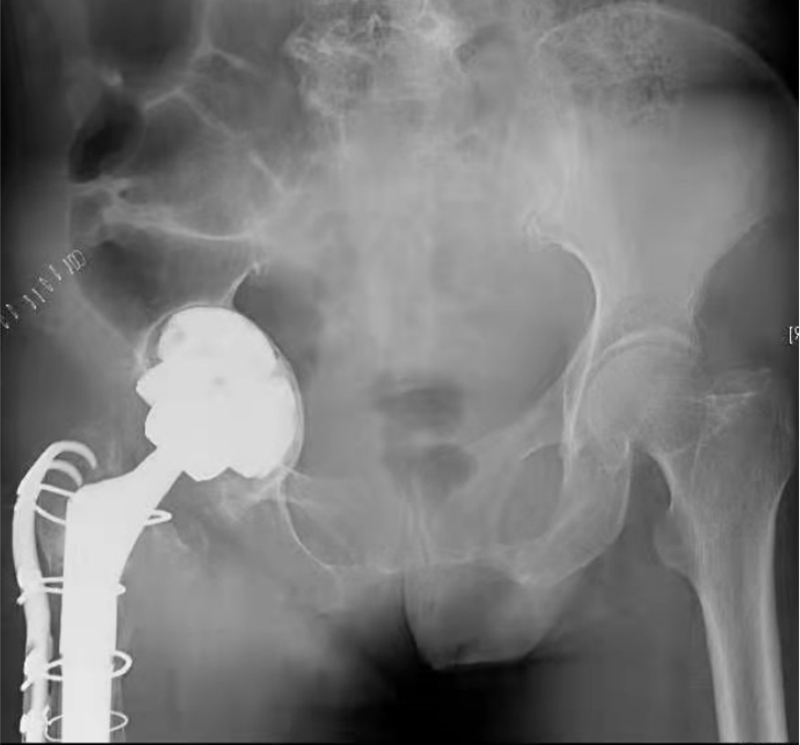

术中,VTS导航系统不仅可以追踪髋臼磨锉、假体位置和前倾角/外展角等关键角度信息,还可以对补块位置进行示踪(图7),将补块和假体安放的位置和角度精确到1mm和1°,从而最大程度地避免了人工操作的误差和对重要生理结构的副损伤,大大提高了骨缺损修复的精准性和手术操作的安全性。术后患者恢复良好,影像学显示补块及假体位置满意(图8),术后第二天即可下地活动。

这是国内外报道的首例采用导航系统完成的合并严重髋臼侧骨缺损的髋关节翻修术,这项技术的成功开展,为复杂髋关节翻修患者带来了福音,引领关节外科的数字化发展迈上了新的台阶。

图8 患者术后X光片,补块和假体位置满意,精准实现了术前规划